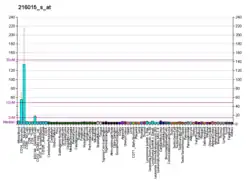

NLRP3 is expressed predominantly in macrophages and as a component of the inflammasome,[7][8]: 436 detects products of damaged cells such as extracellular ATP and crystalline uric acid. Activated NLRP3 in turn triggers an immune response. Mutations in the NLRP3 gene are associated with a number of organ specific autoimmune diseases.

NLRP3 is a component of the innate immune system that functions as a pattern recognition receptor (PRR) that recognizes pathogen-associated molecular patterns (PAMPs).[14] NLRP3 belongs to the NOD-like receptor (NLR) subfamily of PRRs and NLRP3 together with the adaptor ASC protein PYCARD forms a caspase-1 activating complex known as the NLRP3 inflammasome. NLRP3 in the absence of activating signal is kept in an inactive state complexed with HSP90 and SGT1 in the cytoplasm. NLRP3 inflammasome detects danger signals such as crystalline uric acid and extracellular ATP released by damaged cells. These signals release HSP90 and SGT1 from and recruit ASC protein and caspase-1 to the inflammasome complex. Caspase-1 within the activated NLRP3 inflammasome complex in turn activates the inflammatory cytokine, IL-1β.[14]